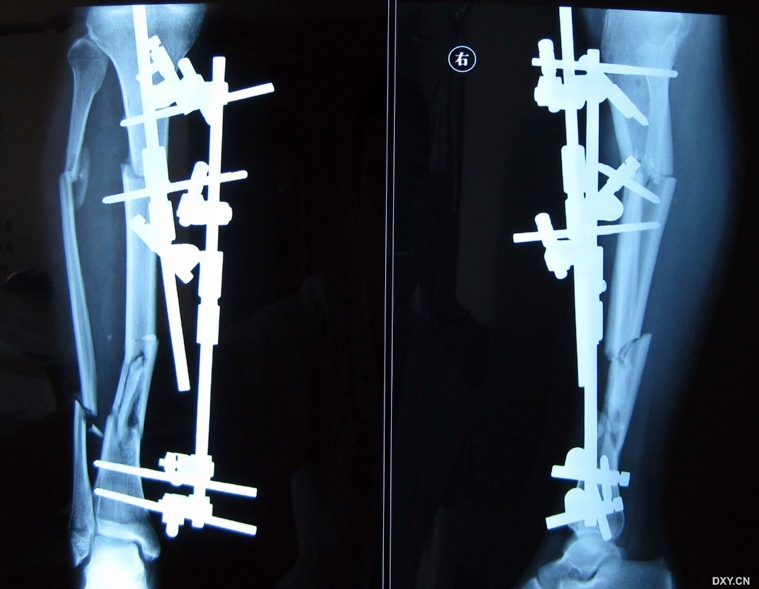

大家看看怎么做?钢板?髓内钉?外固定架?

对于这种复杂的胫腓骨多段开放性骨折如何选择内固定确实是件令人头痛的事。

1. 可以用加长的 LISS 钢板,但对本例来说还不够长。

2. 可以考虑定制钢板,但剥离太多,置入困难。

3. 外固定架,如果是终极固定患者不接受。

4. 钢板接力,开放性创口,放置内侧板有风险。

最终选择髌骨上入路髓内钉固定。